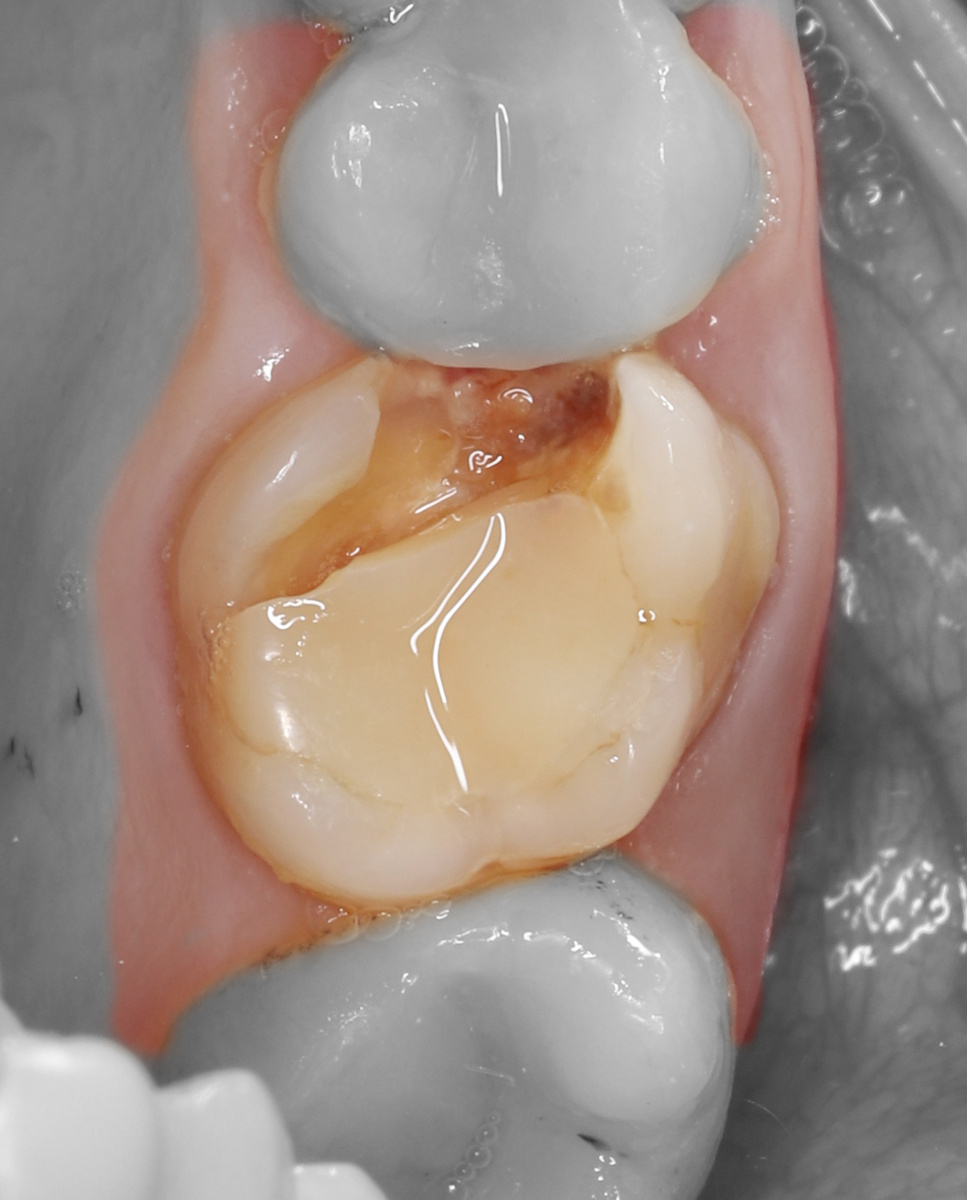

1) Дано: продольный перелом мезиального корня зуба 2.6, зуб признан непригодным к восстановлению.

2) Зуб был сегментирован с помощью фрезы линдемана и удален атравматично.